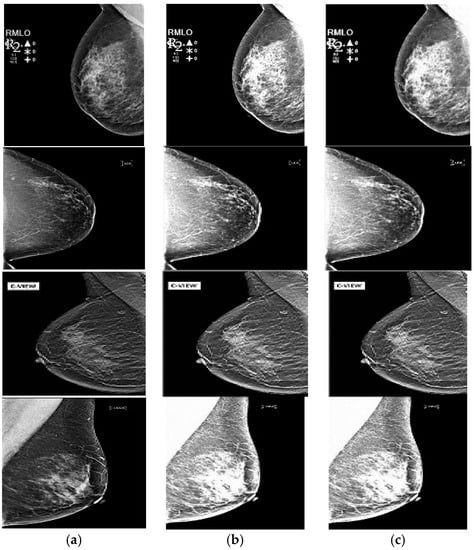

The original source images and enhanced images are then processed via sub-band decomposition using DWT via the suitable wavelet family followed by fusion using the max-max fusion rule. The obtained results are shown in Figure 3, followed by performance measurement using various IQA metrics/fusion metrics and enlisted in Table 1 and Table 2.

Figure 3.

(a) Original images from MIAS, DDSM, and DBT Databases, (b) Enhanced Images obtained via Optimized S-curve Transformation, (c) Fused Images.

As already mentioned, the IQA of test images was carried out using E, EME, and AMBE to quantify the enhancement response, and SD and IQI metrics quantify the fusion response for the original and enhanced images shown in Figure 2 and Figure 3, and their values are tabulated in Table 1 and Table 2, respectively. As per the tabulated results in both tables, it can be observed that the incremental values of quality metrics are seen for the fused image of Figure 3c with respect to the source images in Figure 3a,b. The improvement in values of Entropy and Standard Deviation shows that the fused images have better information restoration and redundancy minimization with respect to the source images. Further, betterment in terms of EME and AMBE depicts that the fusion process has maintained the contrast and brightness of the medical images leading to proper visualization of ROI without the introduction of any other artifacts. The sharpness of the fused image is also improved as shown by enhancing values of IQI.